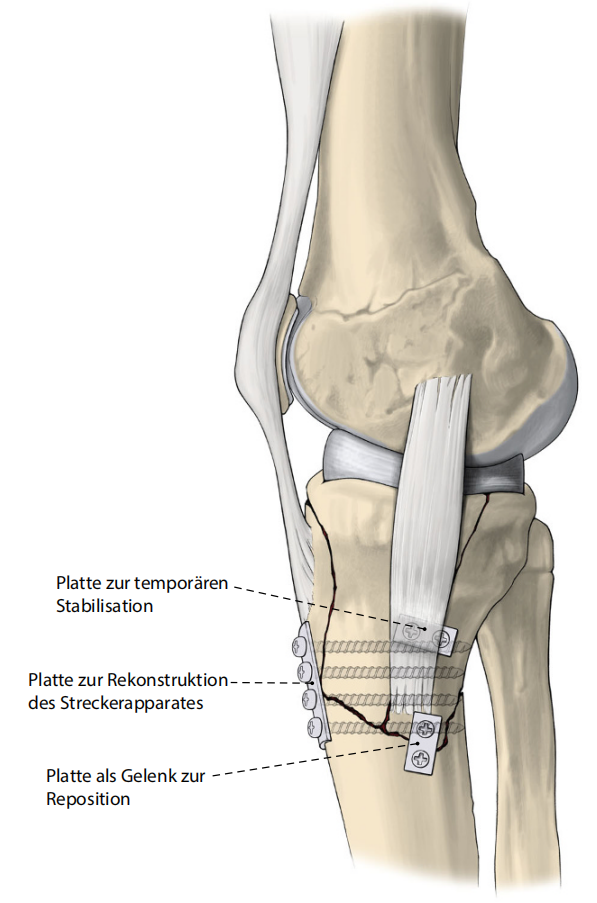

病例2

图16:外翻/屈曲型骨折合并骨质疏松症,累及前柱、内侧柱及后柱。

-

俯卧位扩展后侧入路(罗氏入路,蓝色),安装后侧钢板。

调整为仰卧位(RL)后行扩展外侧入路(红色)。

a–d 术前计划CT(计算机断层扫描)。e, f 术后首次体位验证。